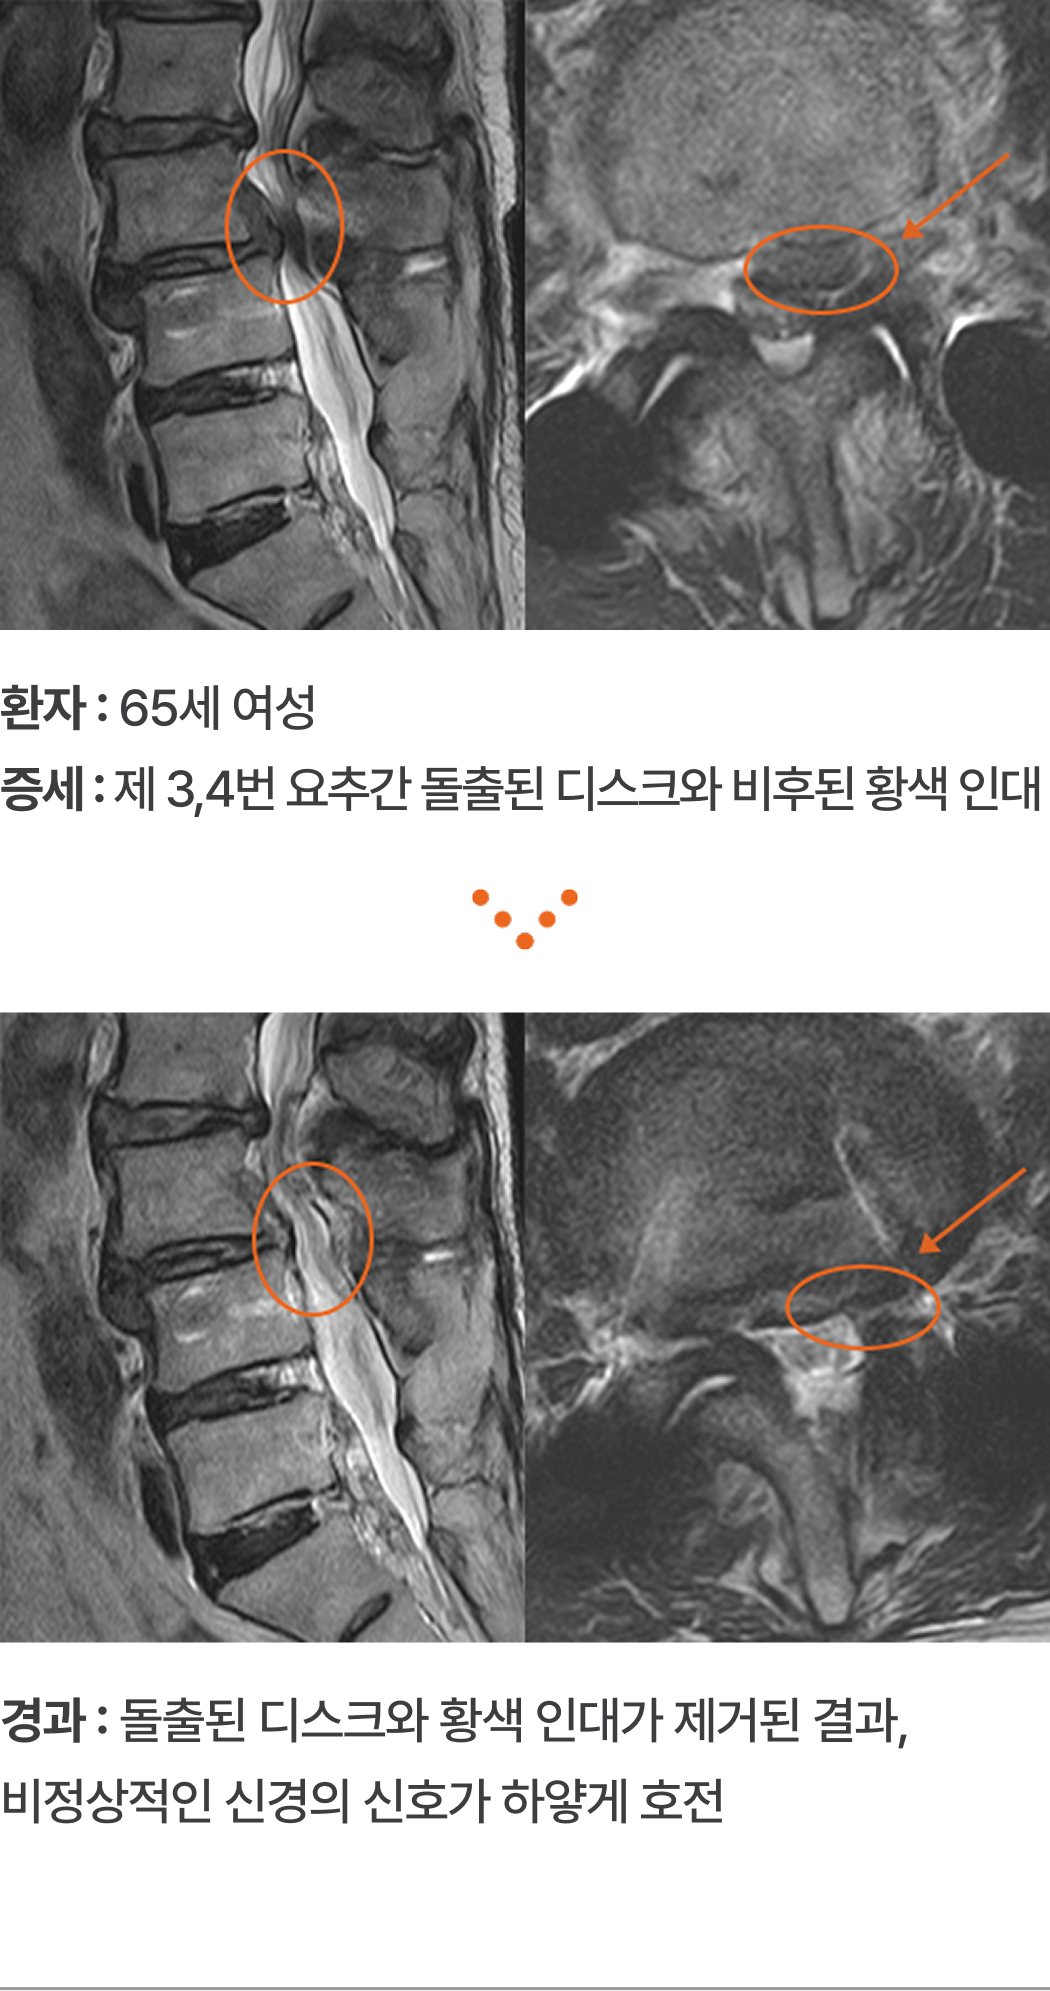

환자 : 65세 여성

증세 : 제 3,4번 요추간 돌출된 디스크와 비후된 황색 인대

경과 : 돌출된 디스크와 황색 인대가 제거된 결과, 비정상적인 신경의 신호가 하얗게 호전